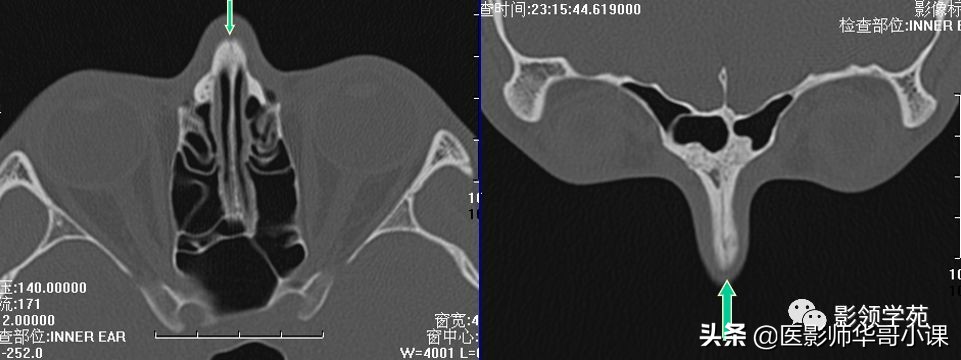

双侧鼻骨骨折

双侧上颌骨额突骨折

鼻中隔骨折